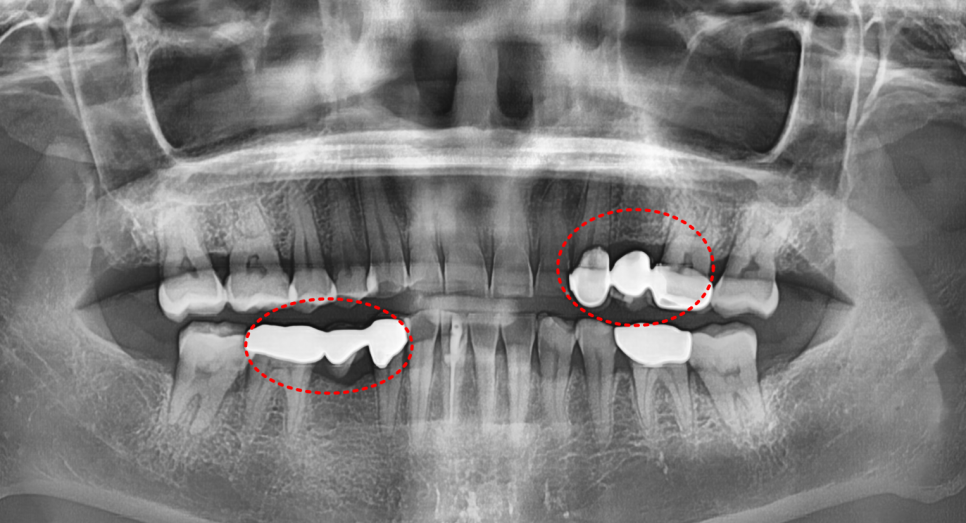

230420

환자분은 아래 앞니 2개와 작은 어금니 1개가 없는 상태였습니다.

230420 누런 치아 연예인치아 처럼 하얗게 만들 수 있나요?

그래서 정면에서 봤을 때 중앙선이 맞지 않습니다.

게다가 왼쪽 위와 오른쪽 아래 브릿지도 오래되어 교체가 필요한 상태입니다.